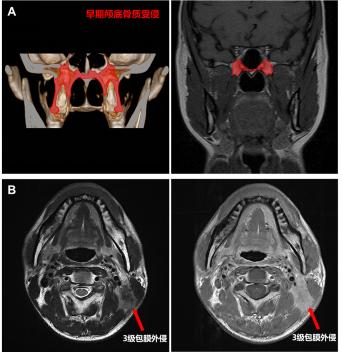

аæ±ÇÑʰ©ÆÊ½â½á¹¹µ÷½âʾÒâͼ

AÔçÆÚ­µ×¹ÇÖÊÊÜÇÖ£º£º£º½öÓÐÒíÍ»»òµû¹Ç»ùµ×µÄ­µ×¹ÇÖÊÊÜÇÖ

B 3¼¶ÁÜͶºÏ°üĤÍâÇÖ£º£º£ºÖ×ÁöÍ»ÆÆÁÜͶºÏ°üĤÇÖÕ¼ÁÜͶºÏÖÜΧÏà½ü½á¹¹